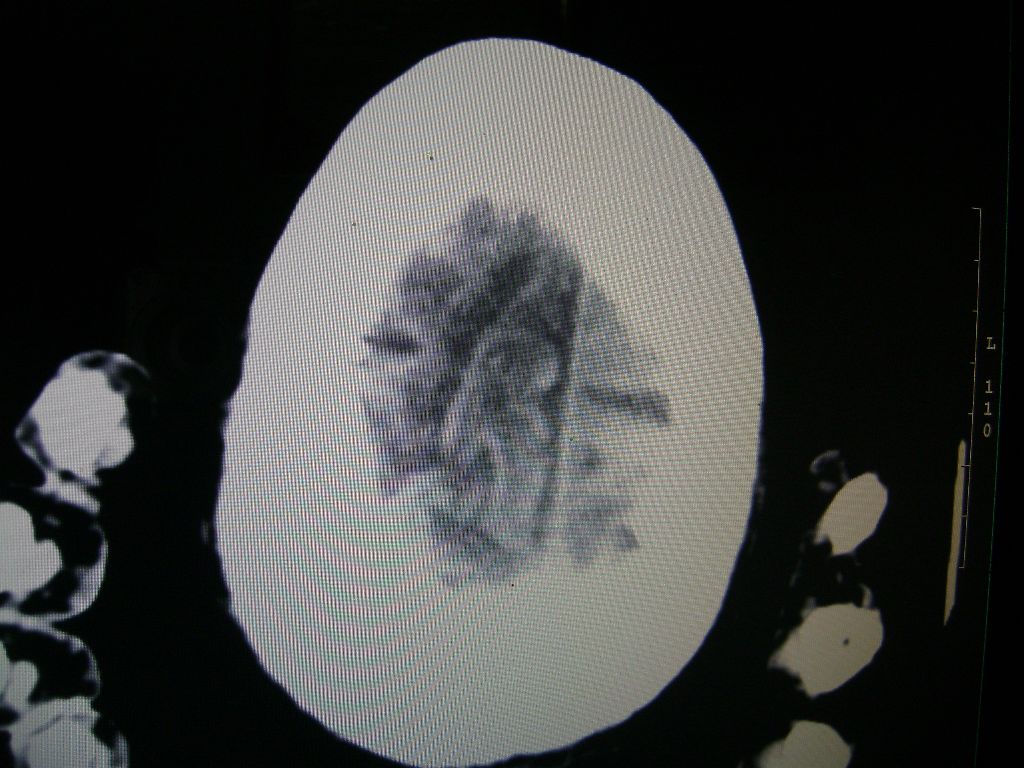

右脑软化灶,考虑再次梗塞,右顶叶高密度影不像是出血,密度很高,建议量ct值!

右侧额颞枕顶叶脑软化灶,脑萎缩,大脑中动脉壁钙化。不支持出血(密度高,边界清且局限)顶枕区似有新发梗塞,建议核磁

1)右侧额颞枕顶叶脑软化灶;其内高密度影,多为钙化灶。2)脑萎缩。3)大脑中动脉钙化。